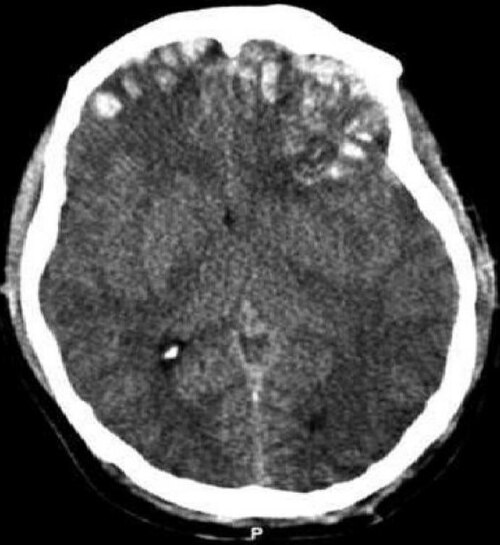

Rehman T, Ali R, Tawil I, Yonas H · CC BY 2.0 · source

Acute assessment protocols draw on emergency medicine systems in hospitals such as Mount Sinai Hospital, Cleveland Clinic, John Radcliffe Hospital and guidelines from the National Institute for Health and Care Excellence and American College of Emergency Physicians. Neurological examination uses Glasgow Coma Scale practices from University of Glasgow; neuroimaging modalities include computed tomography and magnetic resonance imaging developed at institutions like Massachusetts General Hospital, Karolinska University Hospital, Royal Adelaide Hospital. Advanced imaging—diffusion tensor imaging, functional MRI, PET—originated from work at Stanford University, MIT, University College London, McGill University, Karolinska Institutet. Diagnostic biomarkers have been pursued in research at the National Institutes of Health, European Commission consortia, and biotech firms linked with Cambridge, Massachusetts and Silicon Valley innovation hubs.